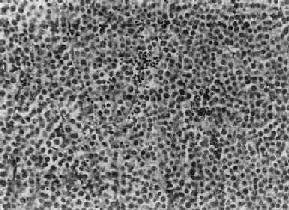

肉眼观,睾丸肿大,有时可达正常体积的10倍,少数病例睾丸大小正常。肿瘤体积大小不一,小者仅数毫米,大者可达十余厘米,通常直径为3~5cm。由于睾丸白膜比较韧厚,未被肿瘤破坏,故通常睾丸的原来轮廓尚保存。切面瘤组织呈淡黄或灰黄色,实体性,均匀一致如鱼肉,其中往往可见到不规则坏死区。镜下,典型的精原细胞瘤有瘤细胞形态结构单一和间质内有淋巴细胞浸润两个特征,(图14-1)。瘤细胞弥漫分布或呈索状结构,细胞的形态一致,与正常精小管内精原细胞相似,瘤细胞大,圆形或多角形、境界清楚、胞浆透明,核大、位于中央,核膜及染色质较粗,有1~2个嗜酸性核仁,核分裂像不多见。间质为纤细的纤维组织或致密的胶原纤维,其中有多少不等的淋巴细胞浸润,有时可有淋巴滤泡形成。

图14-1 精原细胞瘤

瘤细胞大、胞浆透明,核大,核仁明显,间质内有淋巴细胞浸润